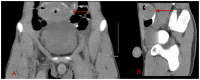

Burkitt lymphoma is a highly aggressive form of Non-Hodgkin lymphoma that responds favorably if diagnosed accurately and treated early. Recognition of the various radiologic manifestations of Burkitt lymphoma can help guide the clinician to expedite appropriate chemotherapy. We present two cases that illustrate different radiologic presentations of this aggressive gastrointestinal malignancy in children. Case 1 features a 7-year-old boy who presented to our hospital with recurrent ileocecal intussusception. Case 2 describes a 16-year-old male with history of blood-streaked stools. Ileocectomy was performed in both cases and histologic analysis showed the "starry sky pattern" and t(8;14) translocation, classic for Burkitt lymphoma. Both patients remain disease-free following surgical excision and chemotherapy.